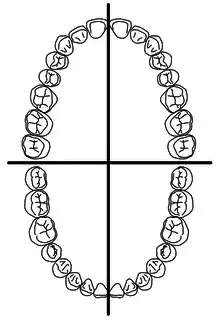

- Quadrant

- The dentition is divided into four quarters. The two dental arches form an oval, which is divided into quadrants which are numbered from 1 to 4:[7]

Dental quadrants

Dental quadrants- Upper right quadrant: upper right first incisor to upper right wisdom tooth

- Upper left quadrant: upper left first incisor to upper left wisdom tooth

- Lower right quadrant: lower right first incisor to lower right wisdom tooth

- Lower left quadrant: lower left first incisor to lower left wisdom tooth